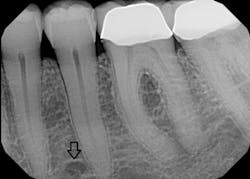

Since only the soft tissues are anesthetized by the mental block, the incisive block is preferred for nonsurgical periodontal therapy procedures. The mental foramen, which opens anteriorly and superiorly, is usually located near the apex of the second premolar (see Figure 2), although studies indicate that it can be located from the distal of the canine to the first molar.3-5 It is advisable to check the radiographs and palpate the area prior to procedures to determine its location. The foramen appears as a round or oval radiolucency on radiographs (see Figures 3, 4) and may be palpable as a concavity or rough elevation.2

Figure 4: Periapical radiograph of left mental foramen. (Courtesy of University of South Dakota Dental Hygiene Program)